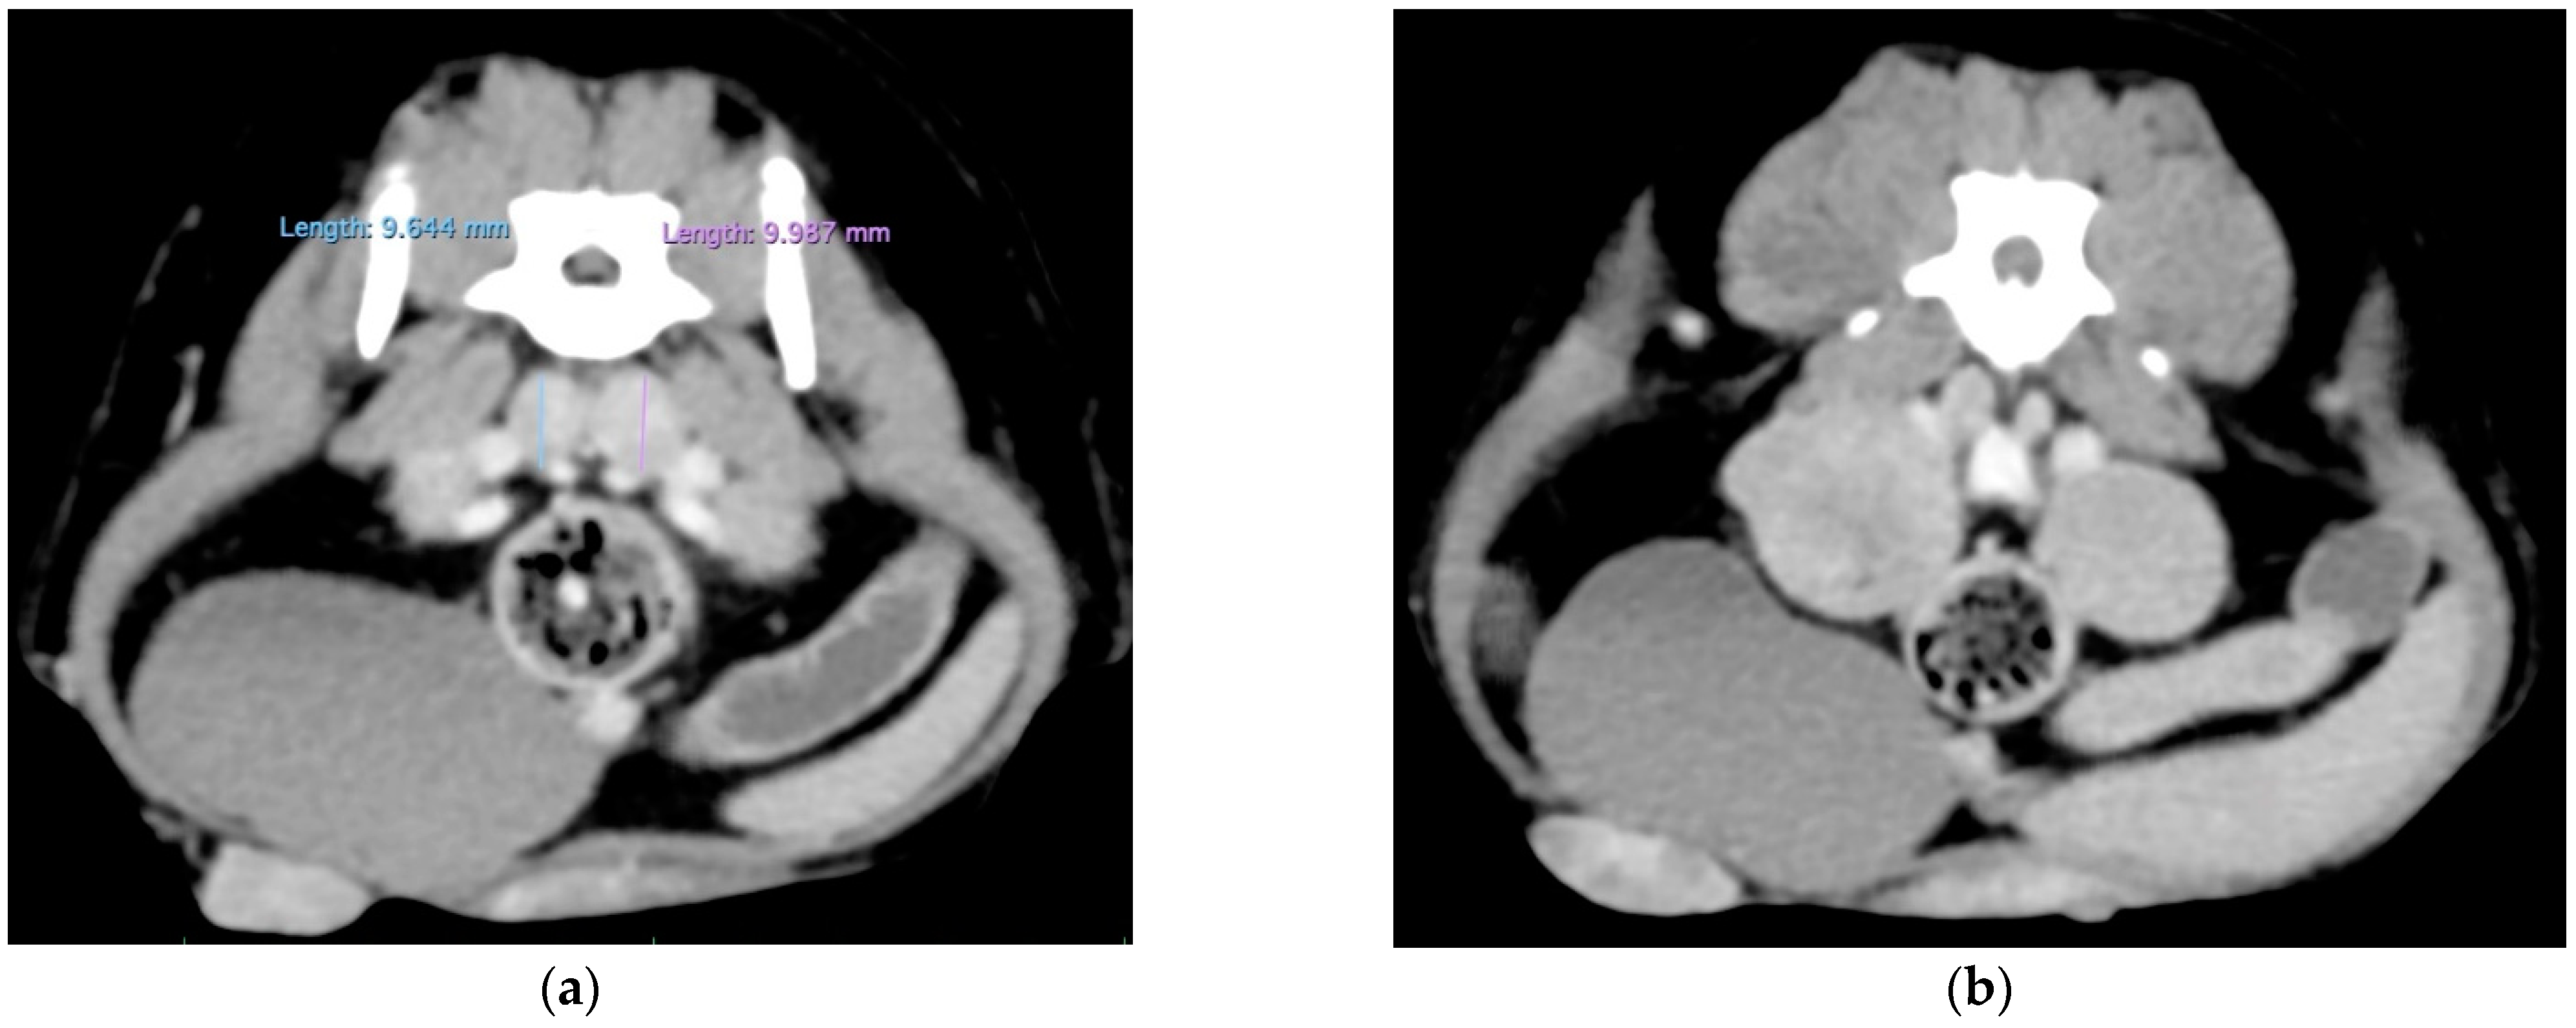

A tomodensitometric examination (whole body) was performed under anesthesia (including premedication with 0.2 mg/kg methadone and 5 μg/kg medetomidine and induction with titrated propofol, followed by isoflurane gas). It revealed the probable infiltration of the iliac, sacral, suprasternal and right inguinal lymph nodes (LNs). No metastases were identified in the lungs, abdominal organs or brain (Figure 2).

Figure 2.

Tomodensitometric examination before surgery. The right inguinal, iliac medial (a), lateral (b), sacral (c) and suprasternal (d) lymph nodes were increased in size and rounded in shape, with a strong homogeneous enhancement following the injection of the contrast medium and were strongly suspected to be infiltrated. No metastases were identified in the lungs, abdominal organs or brain.